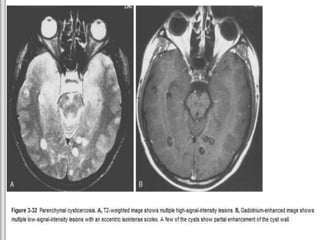

Convexity cysts have a scolex and surrounding inflammation. Inflammation around the

largest cyst “seals” the sulcus and makes it appear parenchymal. “Racemose” cysts without scolices

eccentrically positioned scolex . Note the second granular nodular lesion

Imaging

– Vesicular: Cyst with “dot” (scolex), no edema, no

enhancement. (MRI - cyst is isointense to CSF and scolex is

isointense to white matter)

– Colloidal vesicular: Ring enhancement, edema

striking Cyst contents hyperintense on T1- and T2-weighted images

(proteinaceous fluid), cyst wall is thick and hypointense)

– Granular nodular: Faint rim enhancement, edema

decreased

– Nodular calcified: CT Ca++, MR “black dots”

(**Common to have lesions in different stages)